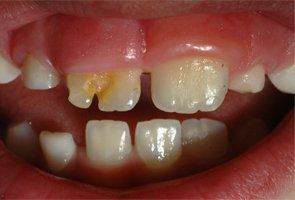

Spätfolge einer Milchzahnverletzung im Alter von einem Jahr: der nachkommende bleibende Zahn weist Form- und Farbveränderung auf.

Ektopischer Durchbruch und persistierender Milchzahn als Folge eines zurückliegenden Traumas. Auf das Trauma läßt schon die dunkle Farbe des Milchzahnes schließen; traumatisierte Milchzähne verfärben sich häufig.